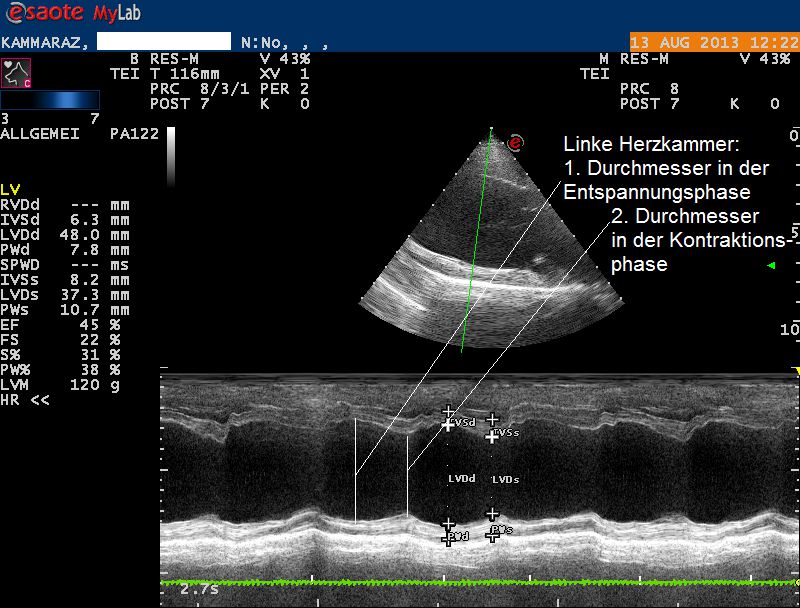

Der Herzultraschall bestätigt den röntgenologischen Verdacht eines Herzproblems: Sowohl die Hauptkammer als auch der linke Vorhof sind bei Karammaz stark erweitert; die Kammer zieht sich ausserdem in der Pumpphase des Herzen zu wenig zusammen, wodurch das Organ zuwenig Blut fördern kann. Im Doppler-Ultraschall ist zu erkennen, dass durch die Erweiterung des Herzen auch die Klappen zwischen linkem Vorhof und linker Kammer undicht geworden sind und Blut beim Pumpen zum Teil nicht in den Körper, sondern zurück in den Vorhof gepumpt wird. Sonografisch ist also ein typisches Bild einer sogenannten Dilatativen Cardiomyopathie (DCM, Herzmuskelerkrankung, welche mit einer Erweiterung einhergeht) vorhanden; als Folge der geringen Pumpleistung des Herzen hat sich ausserdem ein Lungenödem gebildet.